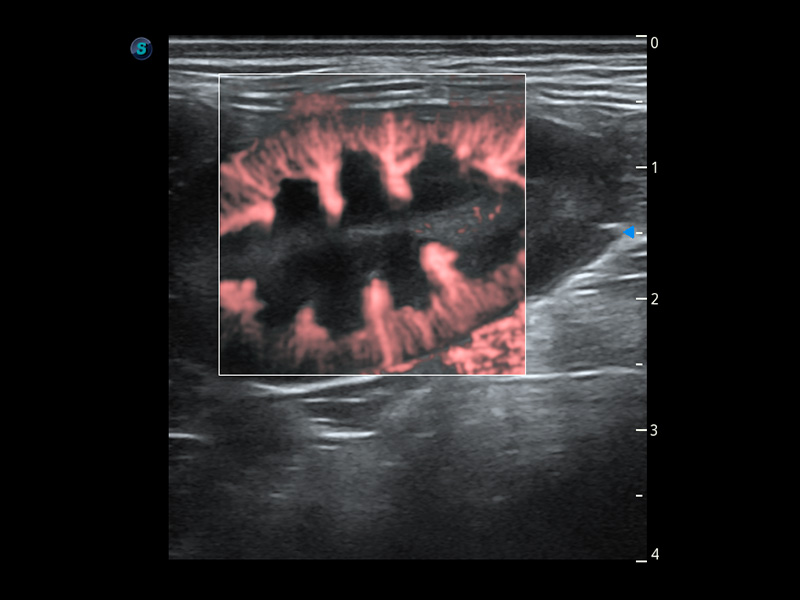

(犬)肾脏血流

PDI 能量多普勒血流

提供高灵敏度和空间分辦率的血流图像,获得更加真实和丰富的诊断信息。

SR Flow 高分辨率血流成像

能够清晰显示细小、低速血流图像,获取传统彩色多普勒技术难以得到的细节和信息。

Micro F 显微血流成像

通过创新的Matrix E自适应滤波器和超长时间域算法,极大提升超低速微细血流的检出能力,同时更精准地滤除软组织和噪声信号,为兽用医生提供以往无法通过常规血流获得的疾病诊断信息。